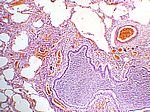

Eitrige Bronchopneumonie, HE